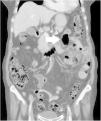

Mujer de 88 años de edad que consulta por dolor mesogástrico de 2 días de evolución, asociado a vómitos y fiebre. Al examen físico presenta dolor a la palpación, con defensa y descompresión positiva; analíticamente: leucocitosis y neutrofilia, la tomografía computada abdominal informa de divertículos yeyunales, cambios inflamatorios en el mesenterio y neumoperitoneo (fig. 1); se realiza laparotomía media, identificando múltiples divertículos en yeyuno proximal, a 40cm del ángulo de Treitz, uno de ellos mostraba una perforación en el borde anti-mesentérico (fig. 2), se realiza resección del área comprometida con anastomosis latero-lateral mecánica; curso postoperatorio favorable, alta al 8.° día. El informe histopatológico fue diverticulitis yeyunal perforada. A diferencia de la enfermedad diverticular colónica, la diverticulitis en intestino delgado es una enfermedad infrecuente; tiene una incidencia alrededor del 1%, permaneciendo asintomáticos en el 70% de los casos, suelen requerir intervención quirúrgica urgente entre el 10-20%. Este proceso inflamatorio puede ser de tipo primario o secundario a la acción de un cuerpo extraño, o por un traumatismo abdominal cerrado. El tratamiento consiste en resección del área de intestino afectada y anastomosis.